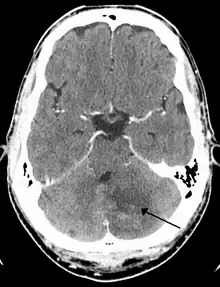

Left sided cerebellar stroke due to occlusion of a vertebral artery